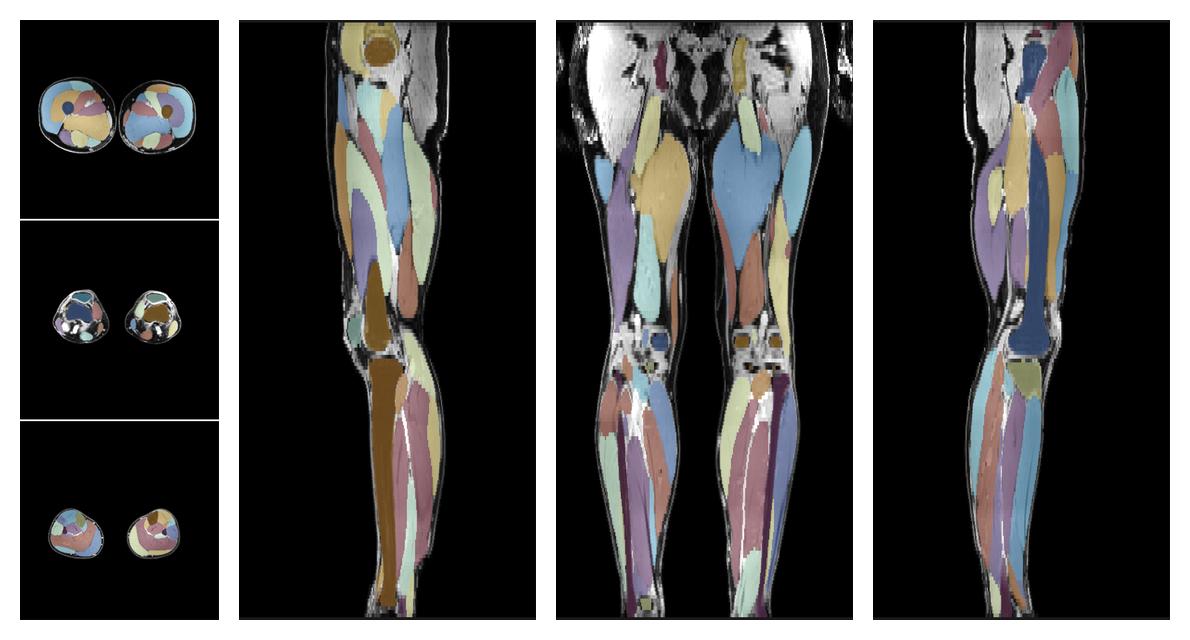

Muscle segmentation

Convolution neural network based (UNET) fiber automated muscle segmentation, for information look here».

• Automated muscle and bone segmentation.

Overlay of automated muscle segmentation labels on dixon water image.